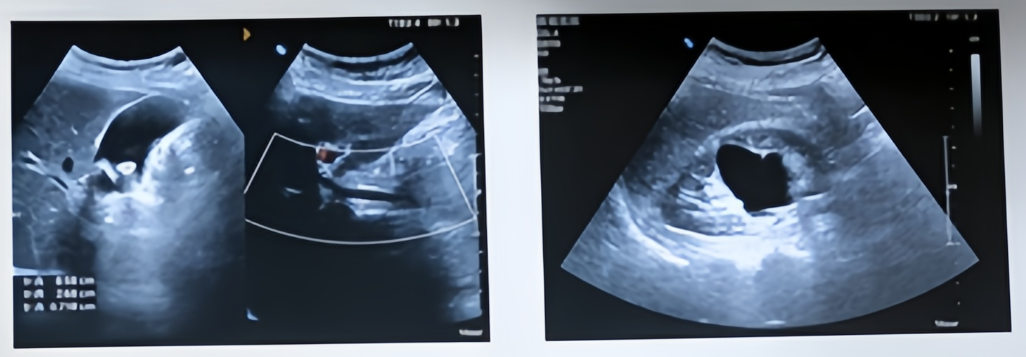

来看这张劝退保胆取石的科普图

保胆取石弊大于利

▶复发率高:保胆好比“割韭菜”,术后5年复发率高达20%-40%。

▶功能已失:病变的胆囊已经失去浓缩和排放功能,留着只是“病灶”。